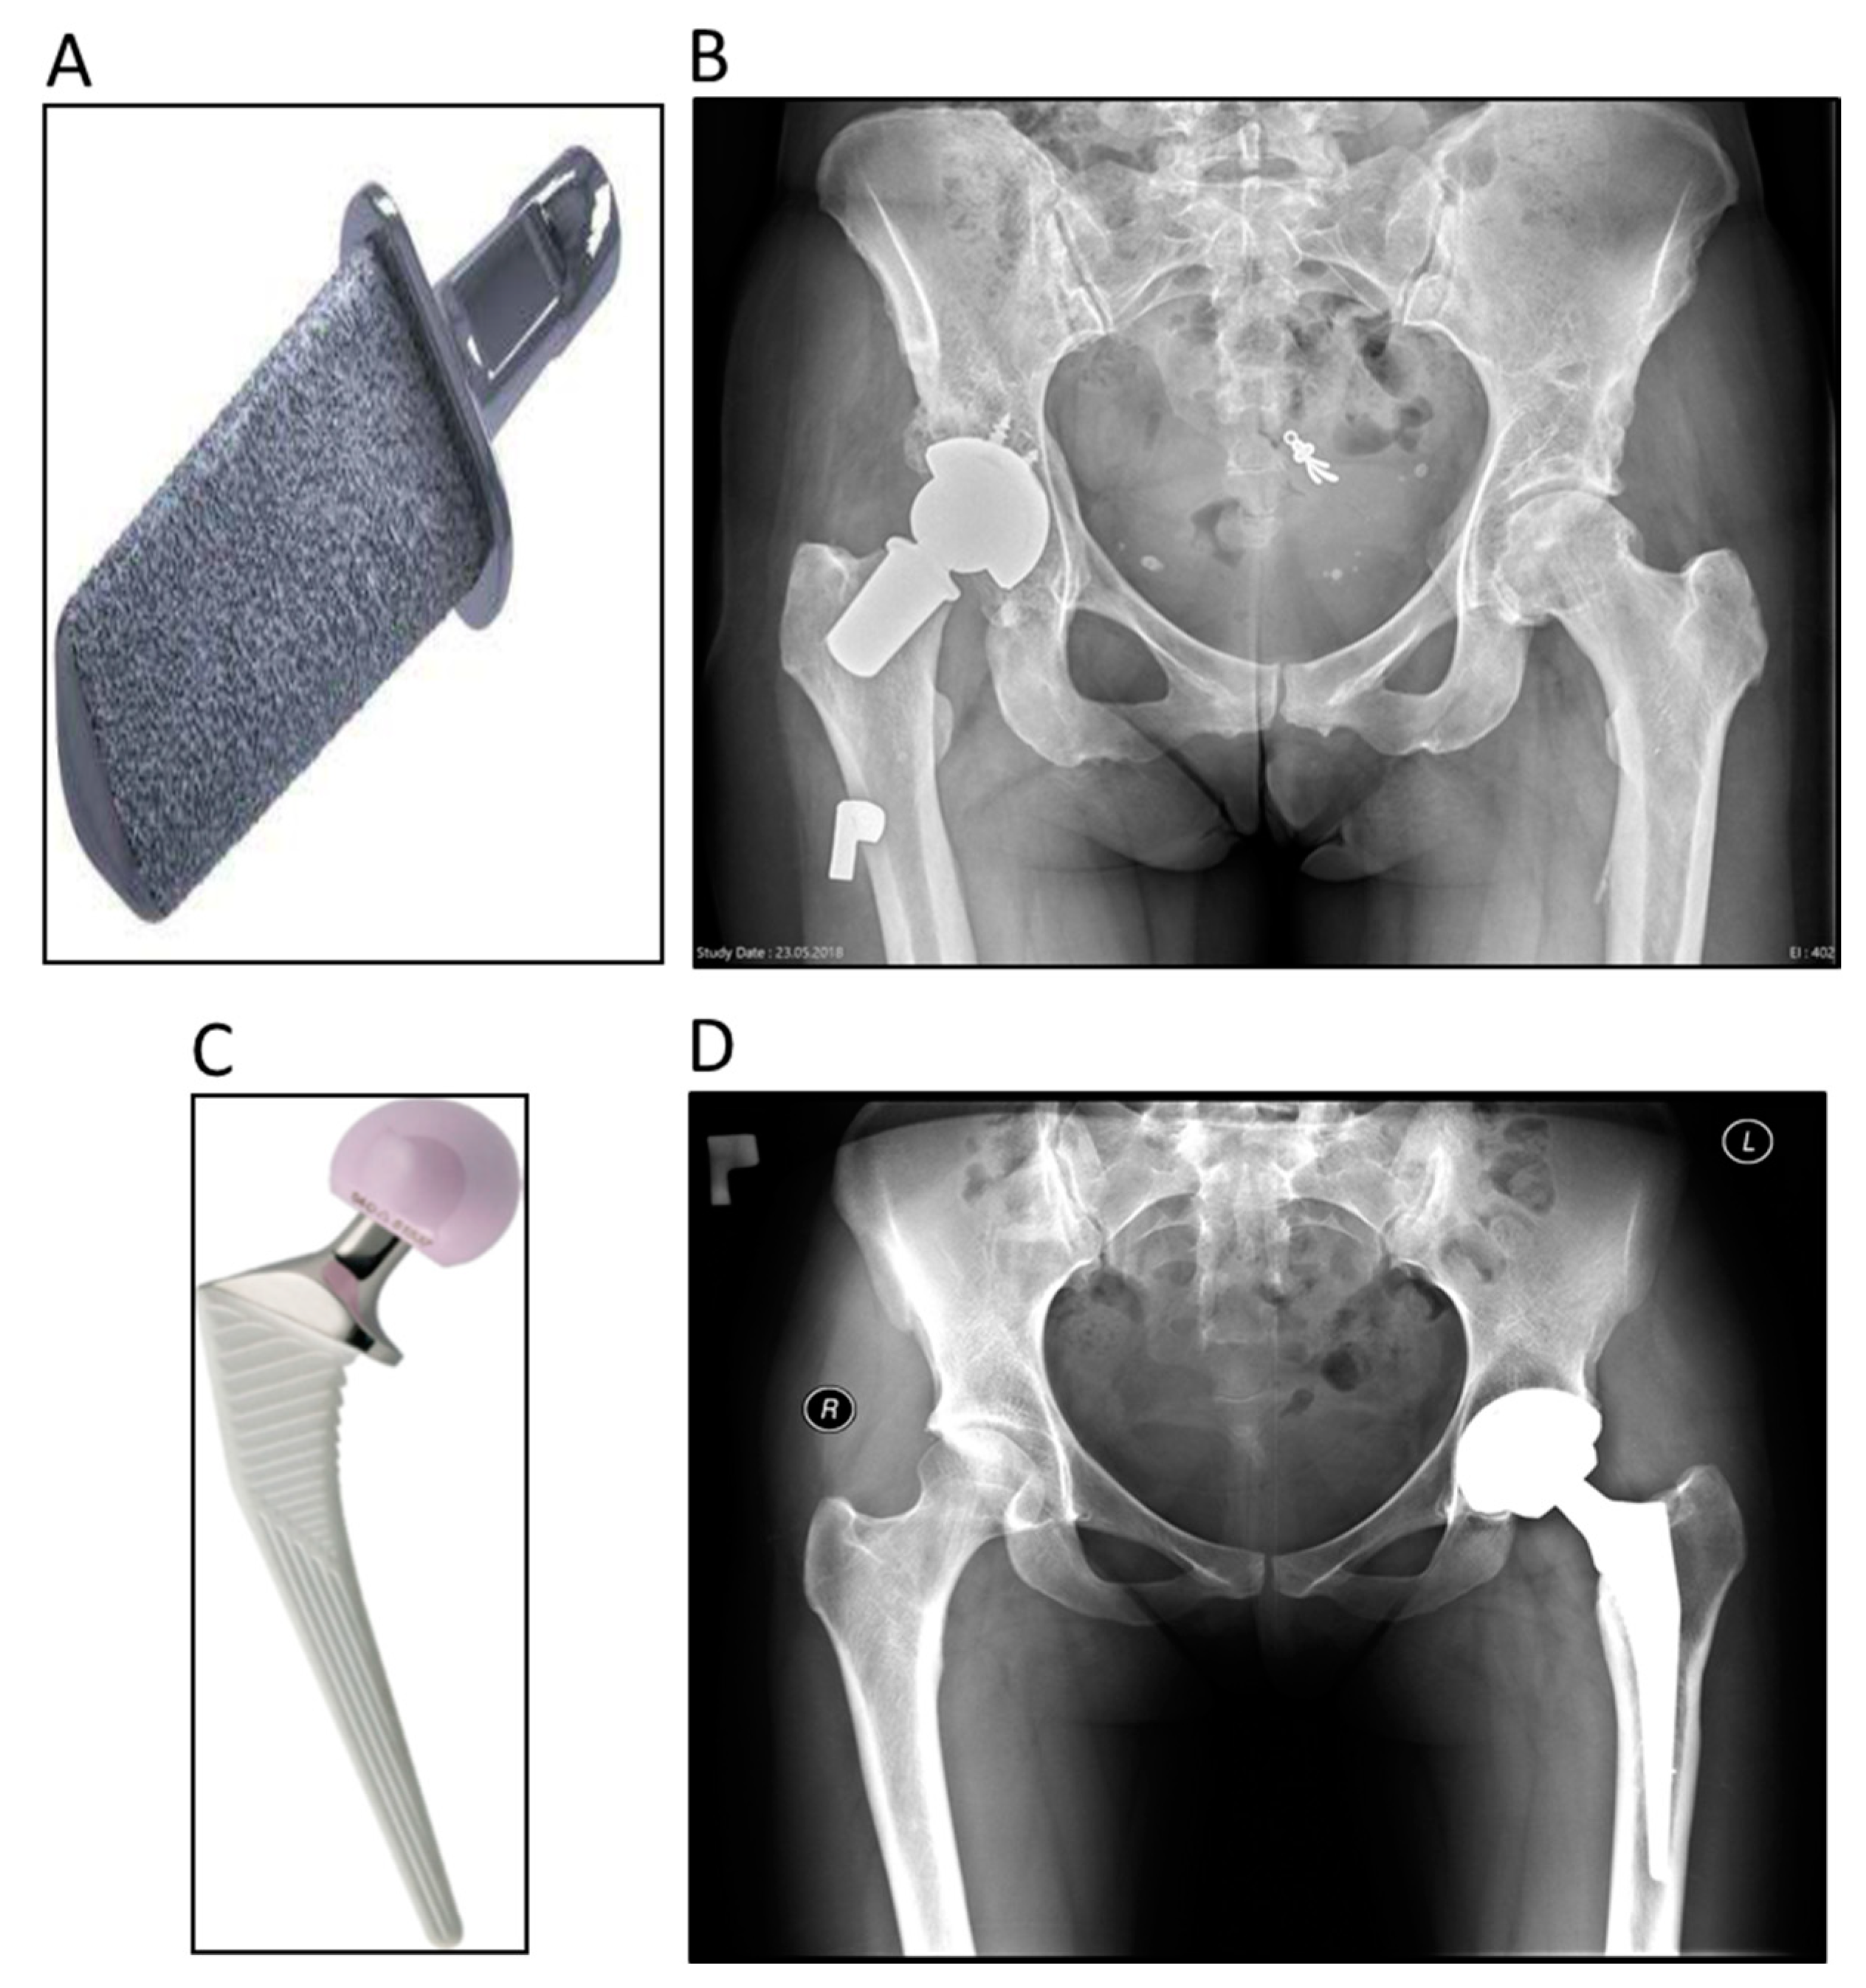

The Primoris™ Femoral Neck (Figure 2A,B) is designed for patients requiring total hip arthroplasty and is dedicated to patients with a well-preserved femoral neck (a not well-preserved femoral neck is defined by 2–7 of the exclusion criteria in Figure 1). The endoprosthesis is made of an alloy of titanium, aluminium, and vanadium (TiAl6V4) and the surface is covered with hydroxyapatite (HA). The cone has a rectangular shape and is available in two lengths. The prosthesis is implanted without the use of bone cement. The cone is adapted with ceramic heads. The acetabular component was a Biomet Exceed cup with a ceramic 36-millimetre insert.

The Corail® system (DePuy Synthes Raynham, MA, USA) (Figure 2C,D) was introduced to the market in 1986 [8]. Since then, this HA-coated cementless rectangular mandrel has become the gold standard among rectangular mandrels because of its excellent clinical results [9]. The acetabular component was a DePuy Pinnacle merged with a ceramic 36-millimetre insert. It is made of TiAl6V4 alloy. The proximal part expands in the sagittal and frontal sections, ensuring good fixation in the proximal metaphysis region of the femur. The distal part tapers downwards, providing good filling of the femoral canal. The stem has two-plane grooves to improve the mechanical stability of the implant. The HA coating prevents the release of metal ions from the stem and ensures good ossteointegration. The HA layer has a thickness of 150 µm and is applied by the plasma method.

Figure 2. The femoral neck prosthesis (Biomet information materials) (A) and postoperative radiograph (B). The conventional hip stem system (DePuy information materials) (C) and postoperative radiograph (D).